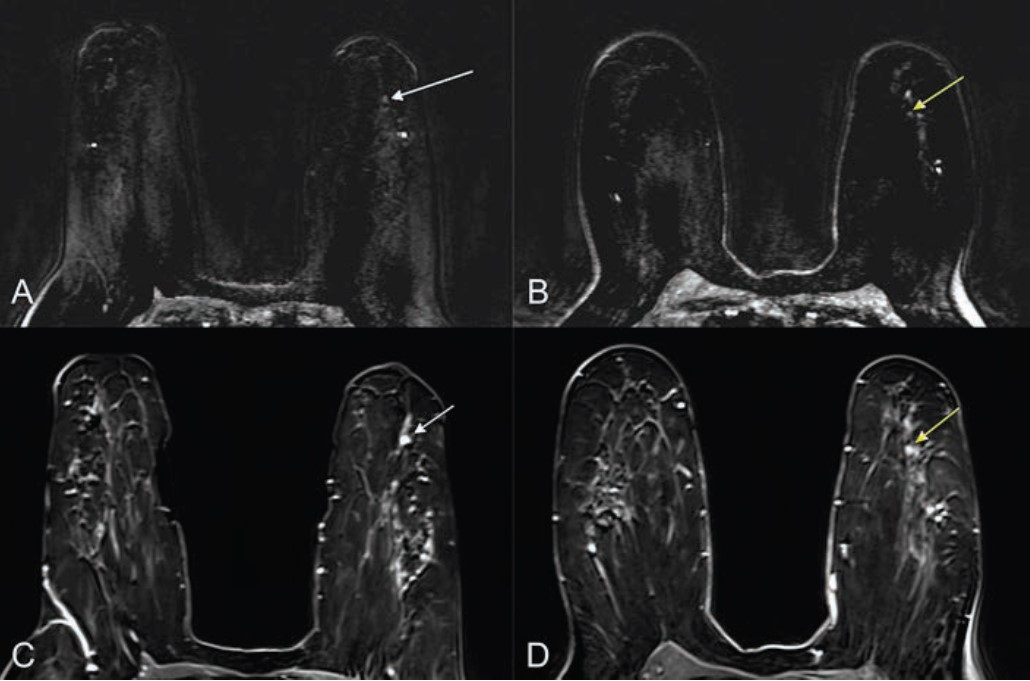

Ultrafast and standard MRI in a 30-year-old woman with triple-negative invasive ductal carcinoma. (A) Ultrafast MRI taken 16.8 seconds after contrast agent injection. (B) Standard MRI taken 58.8 seconds after contrast agent injection. Both images show an oval-shaped, irregular marginated, rim-enhancing mass in the left outer breast. For 3D tumor segmentation, the entire enhanced tumor margins were drawn from top to bottom of each tumor in axial views of U2 phase postcontrast ultrafast MRI and the initial phase postcontrast standard MRI. Among the 14 ultrafast images, U1 is the first phase in which the signal intensity of the hotspot region of interest of the tumor is 10% higher than the average signal intensity of unenhanced images. U2 is the immediate next phase of U1 and the well-established tumor enhancement time.Springer Nature (open access)